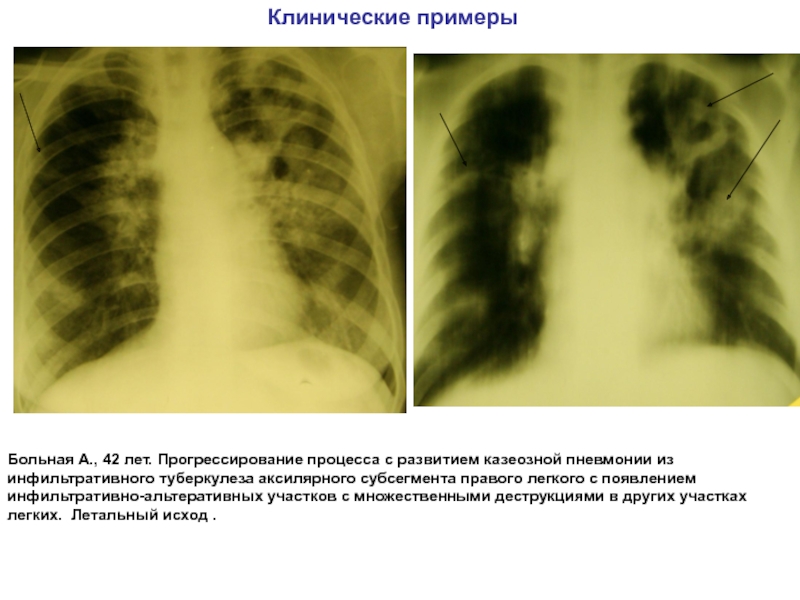

Иллюстрации по теме очагового и инфильтративного туберкулеза

Раздел: Фотодневник открытий